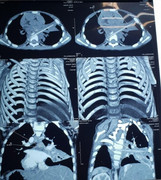

Văn Trường (34 tuổi, An Giang) bị khởi tố, tạm giam vì đánh con riêng của 'người tình' vỡ gan, lá lách gây sốc mất máu dẫn đến tử vong.

Bé trai có nhiều vết thương lớn ở đầu và má trái, tổn thương nghiêm trọng, phải nhập viện cấp cứu khẩn cấp.